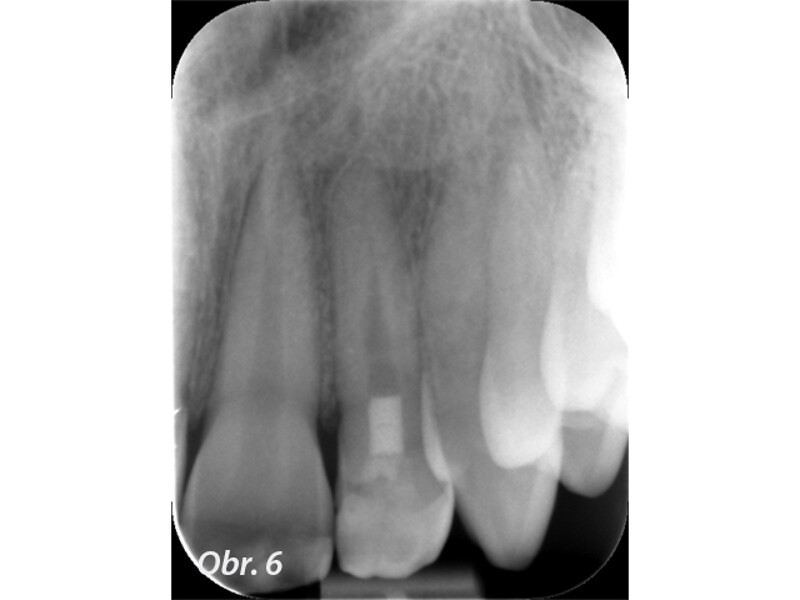

Indikační šíře MTA: Soubor kazuistik